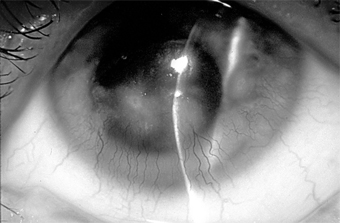

Ocular rosacea is a common complication of acne rosacea and probably occurs more often in light-skinned people, especially of Irish descent, than in dark-skinned people. It is usually a blepharoconjunctivitis, but the cornea is sometimes also affected. The patient complains of mild injection and irritation. There is frequently an accompanying staphylococcal blepharitis. The blood vessels of the lid margins are dilated and the conjunctiva hyperemic, especially in the exposed interpalpebral region. Less often, there may be a nodular conjunctivitis with small gray nodules on the bulbar conjunctiva, especially near the limbus, which may ulcerate superficially. The lesions can be differentiated from phlyctenules by the fact that even after they subside, the large dilated vessels persist.

Microscopic examination of the nodules shows lymphocytes and epithelial cells. The peripheral cornea may ulcerate and vascularize, and the keratitis may have a narrow base at the limbus and a wider infiltrate centrally. The corneal pannus is often segmented or wedge-shaped inferiorly (Figures 5-16 and 5-17).

Figure 5-16

Figure 5-16: Chronic conjunctival injection and inferior keratopathy of rosacea. Note inferior pannus and corneal scarring suggestive of staphylococcal hypersensitivity.